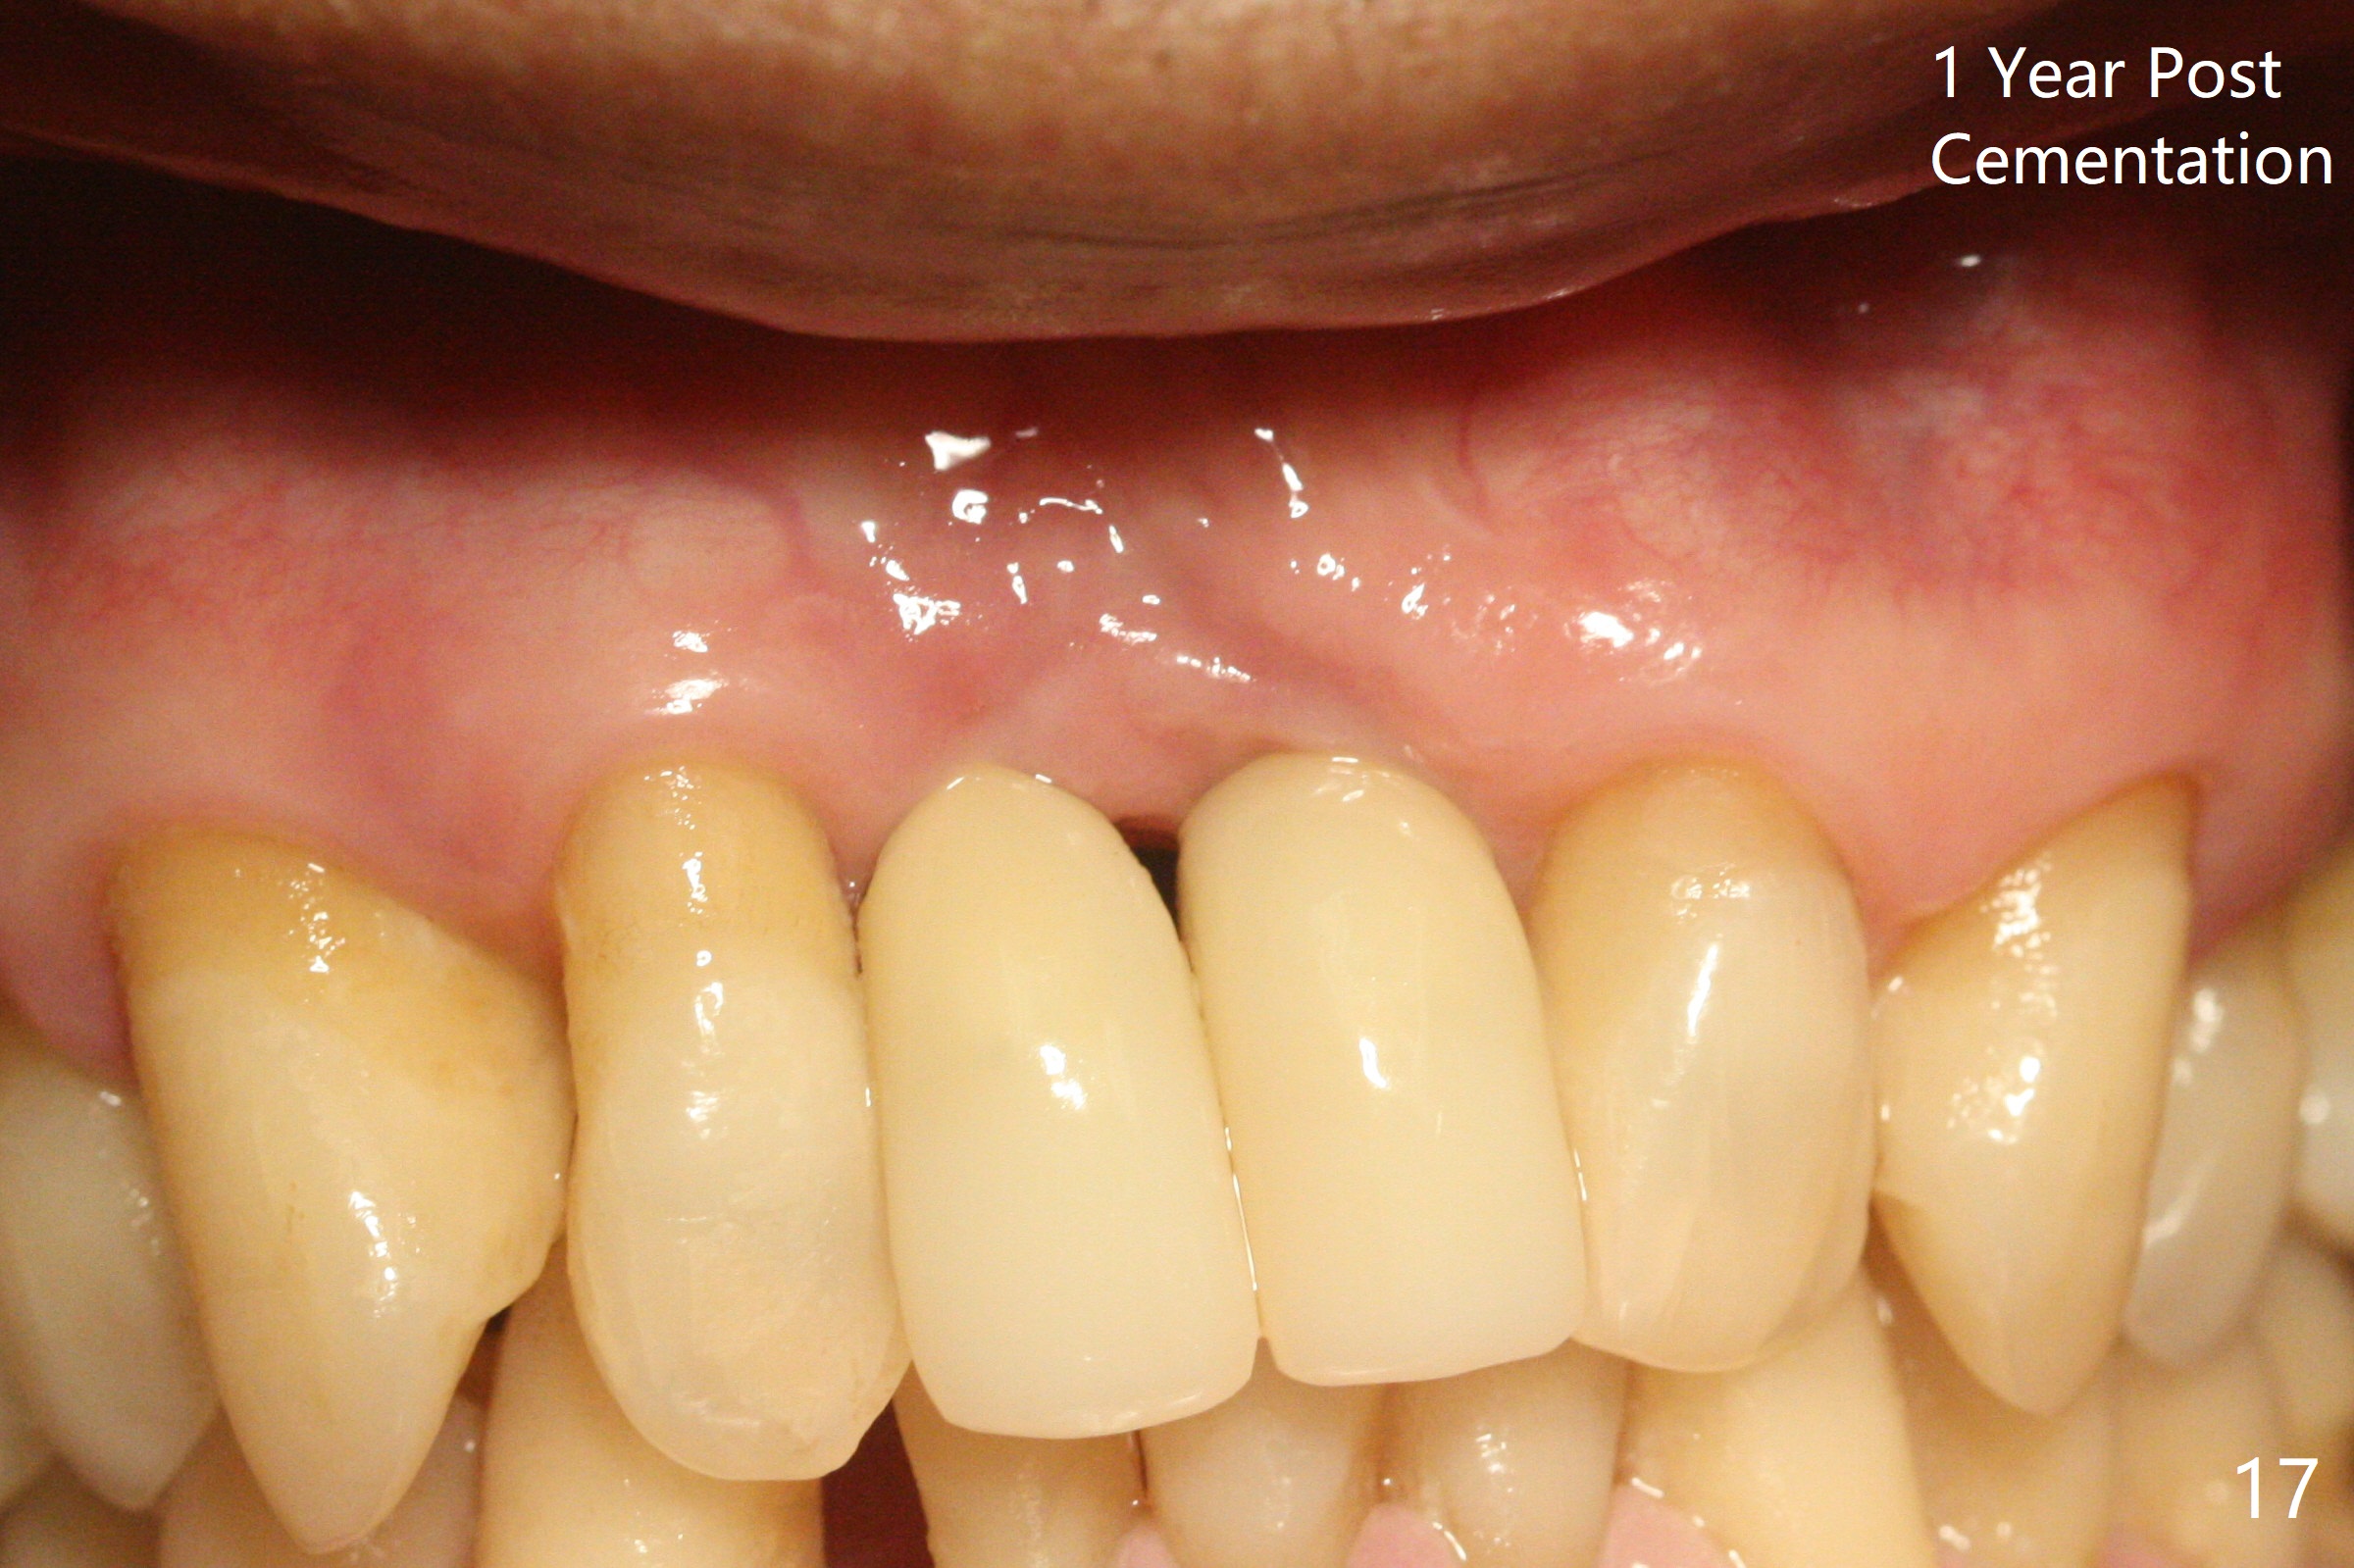

The gingiva remains recessive at #8 and 9 six months post immediate implant placement with bone graft (Fig.1). The buccal plate at #8 is particularly concave before (Fig.2 *) and after (Fig.3) abutment removal. The bony defect repair is assisted by placing a 4 mm tenting screw between the 2 implants (Fig.4) and placing allograft mixed with PRF (as putty) around the screw (Fig.5 (after replacement of the abutments)). The buccal contour improves because of the tenting screw and the bone graft placement (Fig.6 (as well as PRF and 6-month membranes)). The wound dehisces 12 days postop and immediately before leaving country for months (Fig.7). The sutures are removed, Osteogen plug is inserted (Fig.8) and periodontal dressing is applied (Fig.9). PA is taken to show the tenting screw (Fig.10 T). The latter is exposed 3 months postop (Fig.11,12). It appears that gingival graft is a must (Fig.13). Make a palatal stent, remove the temp with abutments and create a bleeding surface before harvesting a large piece of tissue. Connective tissue graft is done 5 months post bone graft (Fig.14). In fact there is no implant thread exposure. In fact the connective tissue graft does not survive. The abutments are re-prepared for pink porcelain (Fig.15). The bone loss is stable 1 year post cementation in spite of incomplete abutment seating (Fig.16). The soft tissue is nearly normal (Fig.17).